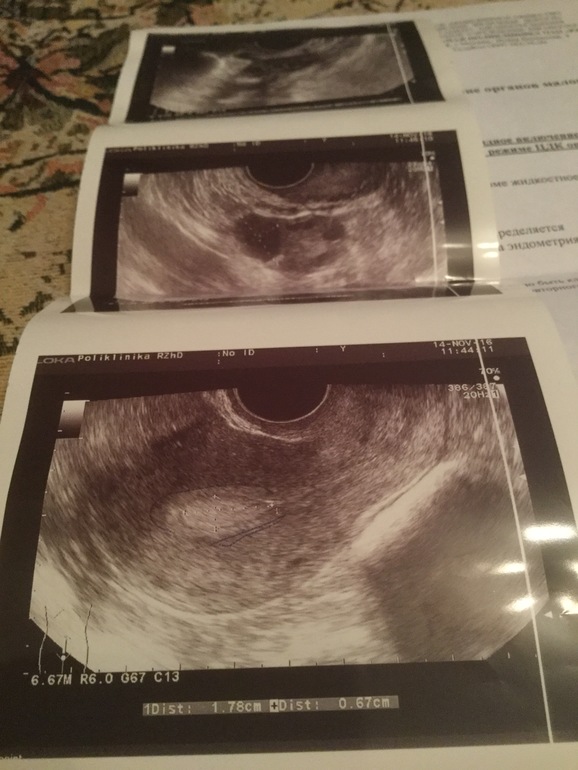

Сегодня 14 ноября иду на узи и там снова полип , таким же размером

Пришла на 7 дц, он полипа не увидел , а моя глазастая узистка говорит полип

Сделал гистероскопию и гистологию бесплатно

Гистология пришла с полипом

Но вот сходила переделала узи в другом месте , ничего не говорила ей , тоже говорит подозреваю полип , но не точно , врачиха грамотная , ген - эндокринолог

Она показала на фото , прям хорошо выделяется из эндометрия , как и месяц назад (((